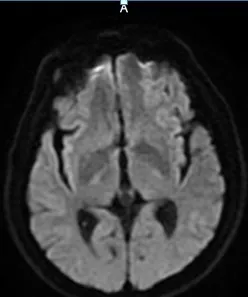

9:40分左右,患者逐渐开始出现烦躁、嗜睡,查体:言语不清,左侧肢体肌力0-1级,急查头颅MRI+MRA+颈部MRA阅片见,右侧基底节区急性脑梗死,右侧大脑中动脉闭塞。

头颅MRI+MRA(08-03日 11:50左右)